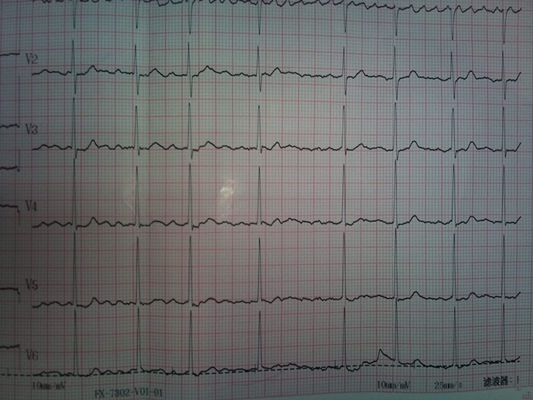

預激綜合症圖片

預激綜合徵心電圖 (9)

預激綜合徵心電圖 (90)

預激綜合徵心電圖 (91)

預激綜合徵心電圖 (92)

預激綜合徵心電圖 (93)

預激綜合徵心電圖 (94)

預激綜合徵心電圖 (95)

預激綜合徵心電圖 (96)